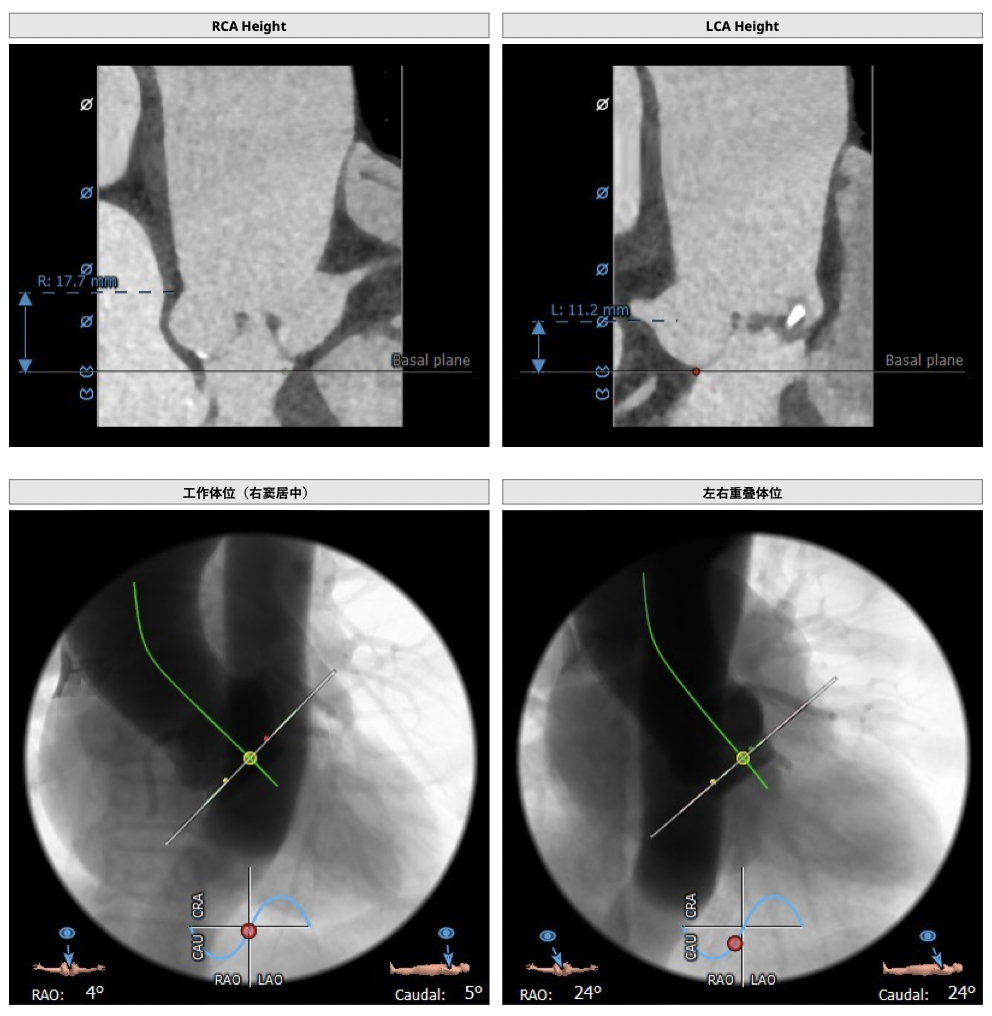

主动脉CT

FEops评估报告

FEops评估瓣周漏

根据FEops量化评估,选用L26瓣膜高位释放会导致8.2ml/s的瓣周漏,而选用L26标准位释放会导致7.4ml/s的瓣周漏,两种释放位置产生的瓣周漏均低于发生中度至重度瓣周漏临界值16ml/s,所以两种释放位置均可以纳入考虑范围,由FEops模拟瓣周漏的3D建模得知发生瓣周漏的主要区域为左右交界处的钙化位置。

L26号瓣膜标准位释放

L26号瓣膜高位释放

FEops评估瓣膜稳定情况

根据FEops评估的L26瓣膜标准位释放结果,发现瓣膜起始位置与稳定位置有较大的改变,判断发生下滑可能性比较大,建议使用VenusA-Plus®可回收输送系统保障手术安全。

瓣膜植入前

瓣膜植入后